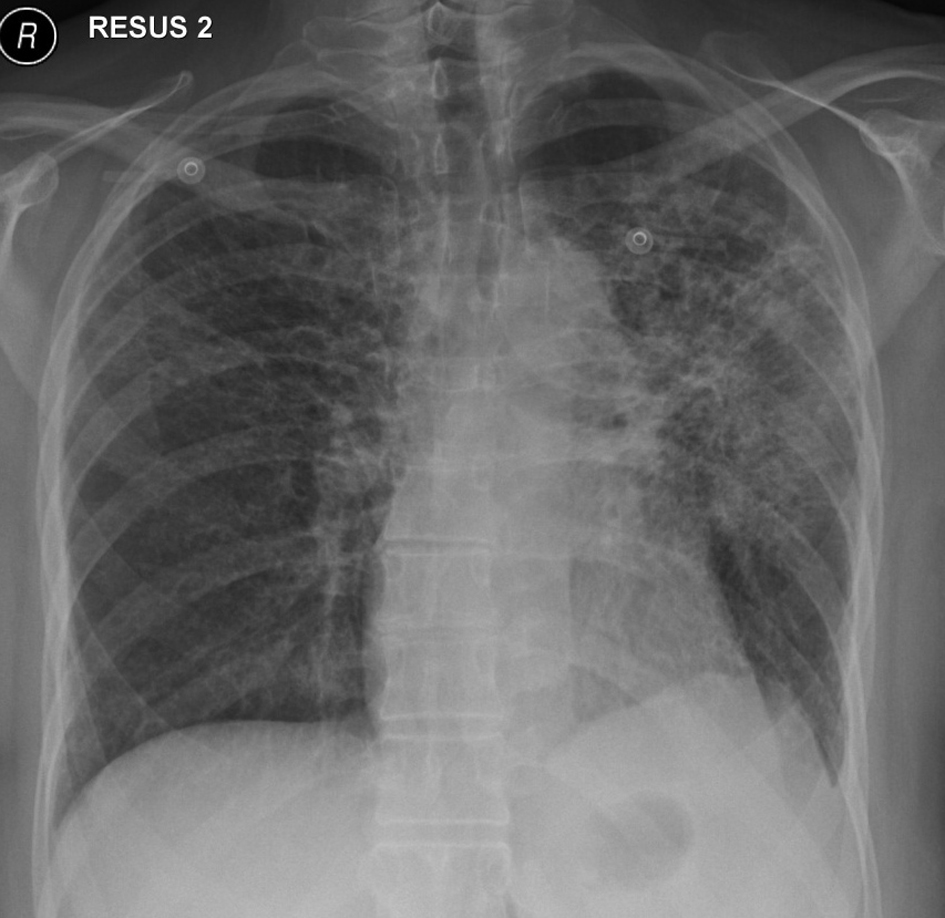

In November 2012, 13 days after the second dose of pemetrexed, the patient presented to our tertiary referral center after developing fever, cough, lethargy and dyspnoea at rest. She had no chest pain or pedal edema. On initial examination, the patient was febrile (temperature 38 °C) and in visible respiratory distress with a respiratory rate of 30 breaths/min and oxygen saturation 78% on room air. An arterial blood gas analysis taken on 8 L/min of oxygen showed hypoxia with a respiratory alkalosis (pH 7.47, PO2 73 mm Hg, and PCO2 32 mm Hg). Chest X-ray showed diffuse reticulonodular opacities in the upper lobes bilaterally (Fig. 2). CT scan revealed widespread interstitial opacity with inter- and intra-lobular septal thickening, and fine nodularity throughout both lung fields (Fig. 3). In some regions the diffuse interstitial opacity gave a ground glass appearance. The radiological changes were diffuse, including areas outside of the previous radiotherapy field. There was no evidence of pulmonary embolus. Her white cell count was not elevated (4 × 109/L; neutrophils 3.5 × 109/L) and hemoglobin level was 101 g/L. Tests of renal and liver function were normal. C-reactive protein was 170 mg/L (normal < 8 mg/L). She was commenced on broad spectrum intravenous antibiotics and transferred to the intensive care unit (ICU) due to ongoing hypoxia and respiratory distress. In the ICU she was commenced on intravenous dexamethasone and placed on non-invasive ventilation. She improved rapidly over the next 3 - 4 days. Repeated blood cultures and induced sputum did not reveal evidence of a typical or atypical infective cause. Bronchoscopy was not performed as the patient was not fit for the procedure whilst acutely unwell. She improved rapidly with conservative management.

![]() Click for large image | Figure 2. Chest X-ray on initial presentation, showing diffuse bilateral reticulonodular opacities in the upper lobes. |